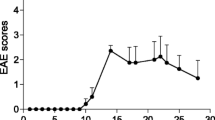

EAE model and study design

The severity of the EAE developed in the Lewis rats was heterogeneous, and four of the animals had an unexpected relapse after the initial EAE phase. Before the PET imaging analysis, rats were divided into three groups based on the day of incidence, severity of the clinical signs, the length of the first clinical period, and the presence of relapses. Seven rats developed mild EAE, six rats developed severe acute EAE, and nine rats developed severe-relapsing EAE including four relapsing rats. One EAE rat did not develop any clinical signs (Fig. 2a–d). One group immunized with CFA (n = 4) was used as control for PET imaging. All EAE rats were imaged at the peak of the EAE (maximum of the clinical signs) and at the recovery phase. Five rats of the severe-relapsing group were additionally imaged during the relapsing phase (days 24–26 post-immunization) including 2/5 that relapsed and 3/5 with no relapse. The CFA control group was imaged at the same time post-immunization as the EAE rats for comparison. The intervention overview for the different groups is summarized in Fig. 2e–i.

Clinical scores of EAE animals that developed severe-relapsing (n = 9) (a), severe acute (n = 6) (b), and mild acute (n = 7) (c) EAE. Table summarizing the information for the different EAE groups (d). Experimental planning of PET imaging in different EAE groups (severe-relapsing (e), severe acute (f), and mild acute (g)), blocking group (h), and control CFA group (i). Arrows are showing when PET imaging was performed